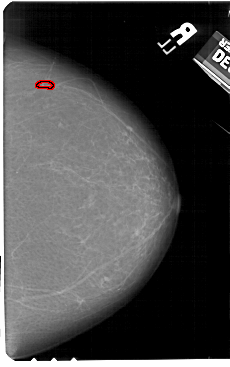

A_1601_1.RIGHT_MLO

RIGHT_MLO LINES 5461 PIXELS_PER_LINE 3601 BITS_PER_PIXEL 12 RESOLUTION 43.5 OVERLAY

FILE: A_1601_1.RIGHT_MLO.OVERLAY

TOTAL_ABNORMALITIES 1

ABNORMALITY 1

LESION_TYPE CALCIFICATION TYPE PLEOMORPHIC DISTRIBUTION LINEAR

ASSESSMENT 4

SUBTLETY 2

PATHOLOGY BENIGN

TOTAL_OUTLINES 1

BOUNDARY